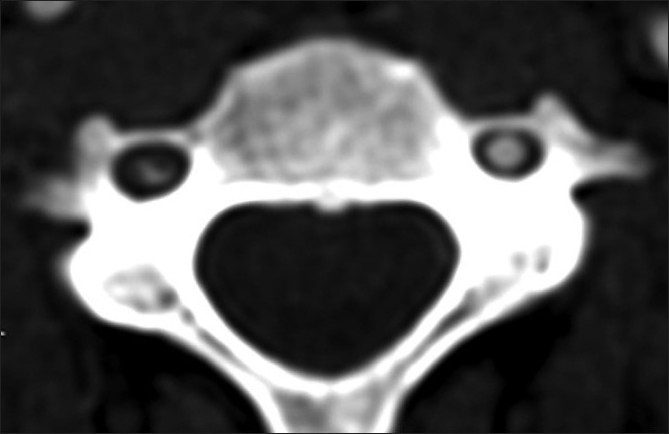

Figure 3.

Axial 2 mm MIP at the level of C1.The left vertebral artery is normal. No wall can be identified as is the usual situation. On the right, there is irregular tapered occlusion of the V3 dissected segment. There is also evidence of vessel wall thickening